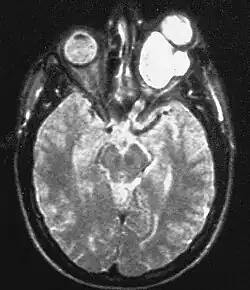

| Magnetic resonance image of a large retrobulbar optic nerve tumor causing massive proptosis | |

Optic nerve gliomas are diagnosed using magnetic resonance imaging (MRI) and CT scans.[5] The tumor adopts a fusiform appearance, appearing wider in the middle and tapered at the ends.[5] Enlargement of the optic nerve along with a downward kink in the mid-orbit is usually observed.[5] While CT scans allow for optic nerve evaluation, MRI allows for intracranial evaluation to observe if the tumor has extended to other regions such as the optic chiasm and hypothalamus.[6]